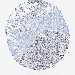

CANCER BREAST CANCER Show tissue menu

BRCA TCGA BRCA VALIDATION PROTEIN EXPRESSION